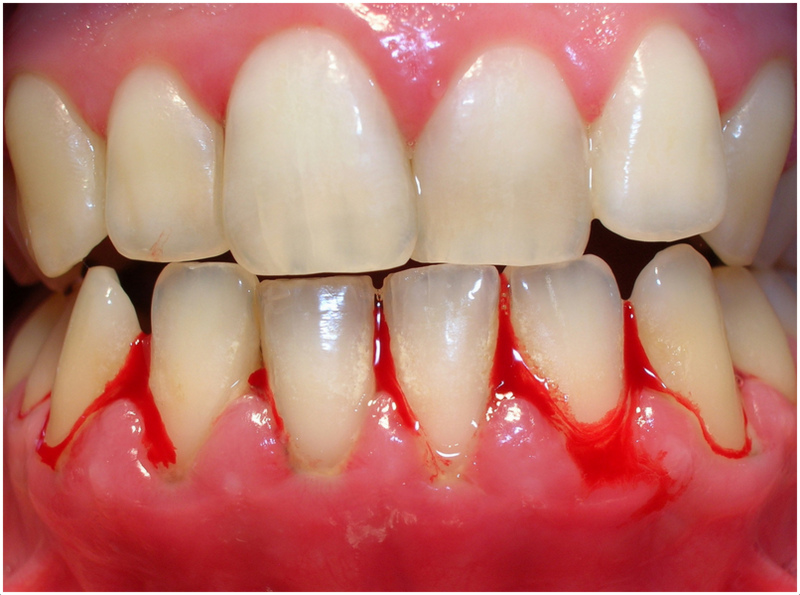

Parodontitin əsas əlamətləri bunlardır:

- Diş ətində şişkinlik və qızartı

- Diş ətində qanamağa meyllilik